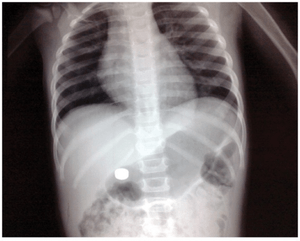

Button battery in stomach on KUB.

- Button batteries may present with "double-ring sign"

Button Battery

- True emergency if located in esophagus

- Perforation can occur within 6hr of ingestion

- via direct pressure or electrical conduction leading to liquefactive necrosis

- Obtain urgent endoscopic removal

- Perforation can occur within 6hr of ingestion